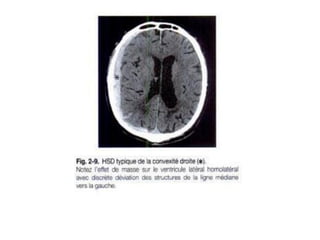

Hématome sous dural : H.S.D

• TDM :

Stade de début: formation spontanément

hyperdense en croissant

Stade sub Aigu: aspect isodense

Stade chronique: hypodense (plusieurs

semaines après le traumatisme )

Recherche de signes d’engagement .

Hématome sous dural: H.S.D C’est une collection de sang extra axiale péri cérébrale entre la dure mère et l’arachnoide secondaire à une plaie d’une veine corticale • Il est aigu , subaigu ou chronique remontant à plusieurs jours voire plusieurs mois • S’accompagne de troubles neurologiques RX CRANE : crâne normal syndrome d’HTIC parfois calcifications: lame ou plaque calcifiée (HSD CHRONIQUE)

• TDM : Stadede début: formation spontanément hyperdense en croissant Stade sub Aigu: aspect isodense Stade chronique: hypodense (plusieurs semaines après le traumatisme ) Recherche de signes d’engagement .